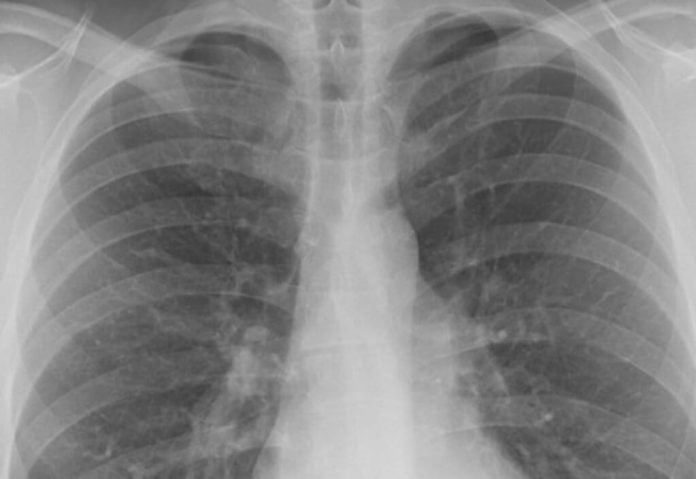

Plămânii au încă o funcţie, despre care nu se știa. Produc trombocite, adică acele celule care opresc sângerarea.

Este descoperirea revoluționară pe care au făcut-o cercetătorii de la Universitatea California.

Noile analize arată că în plămâni se produc 10 milioane de trombocite pe oră. Această descoperire contrazice asumpția care circulă de zeci de ani și care susține că măduva osoasă este responsabilă de producerea tuturor componentelor sângelui, conform Science Alert.